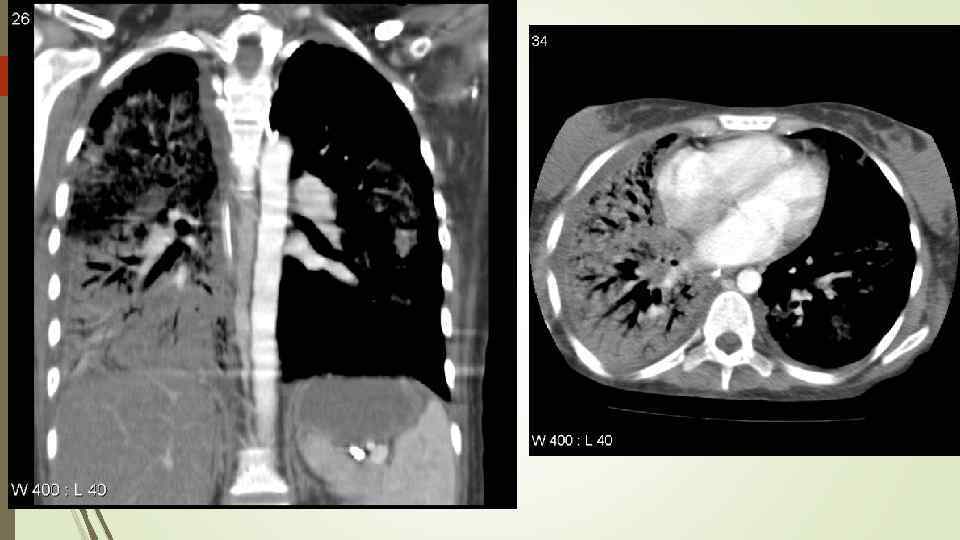

Necrotizing Pneumonia

Necrotizing Pneumonia